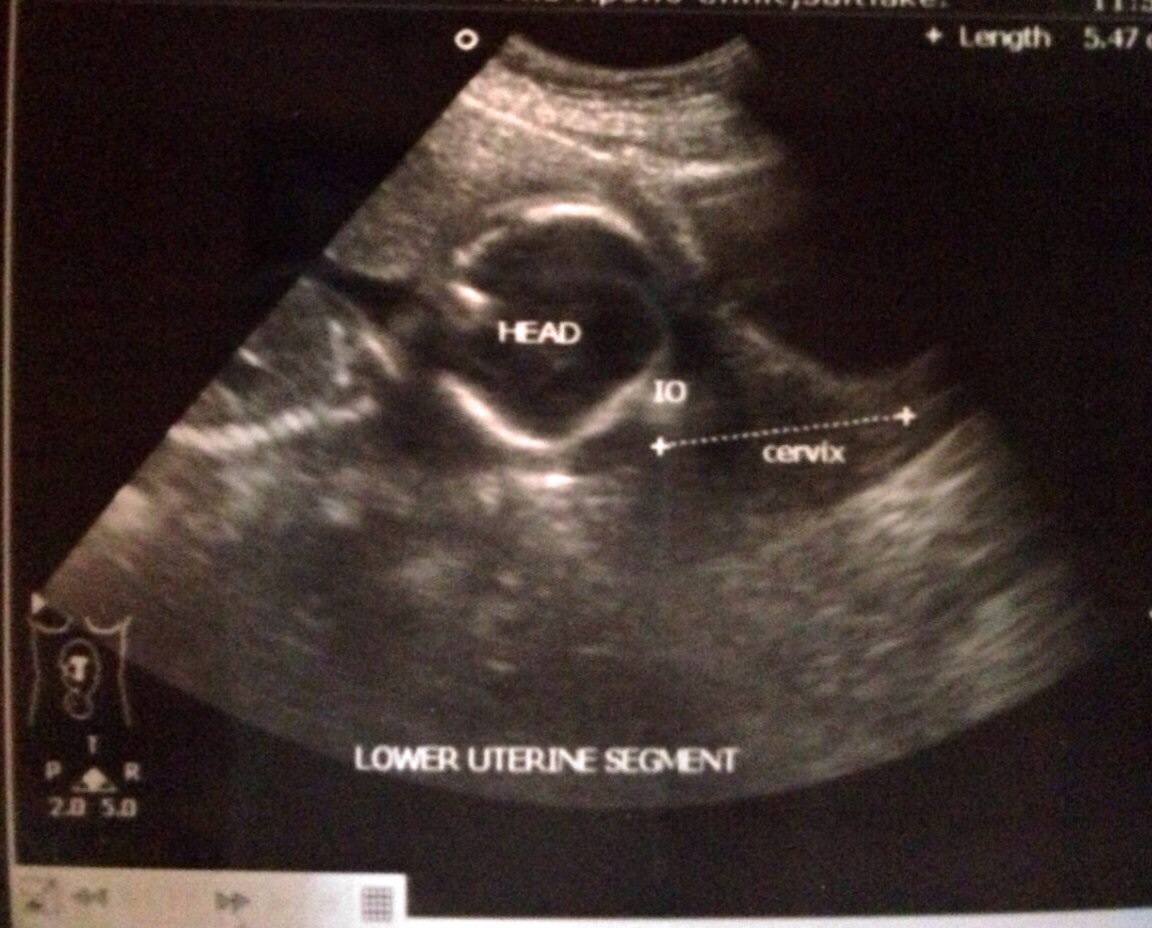

This 20+3 weeks scan. Pls guess the gender!Attachment 14247Attachment 14248Attachment 14249Attachment 14250